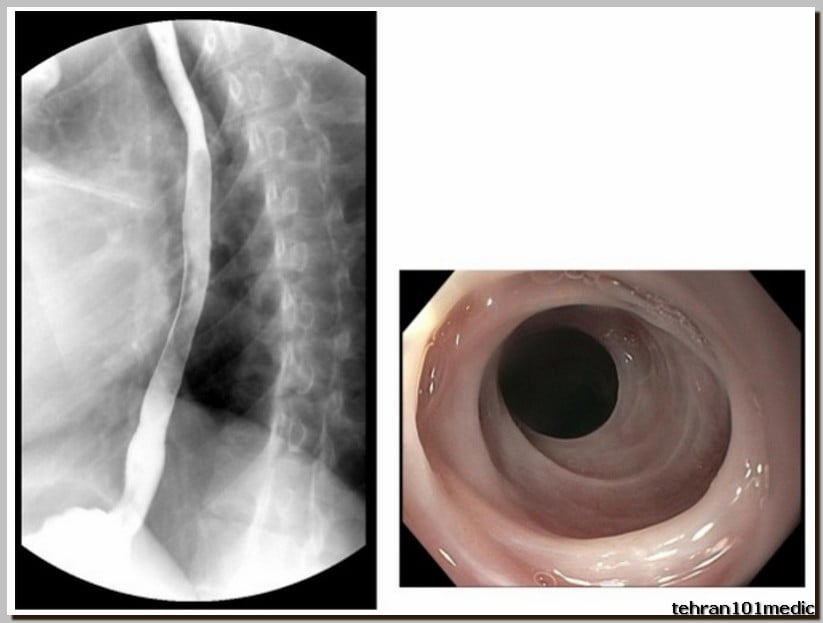

پرتونگاری مری یک روش تصویربرداری پزشکی است که با استفاده از پرتو X-ray انجام میشود. در این روش تشخیص، پزشک معالج تصاویری از داخل مری تهیه میکند. پرتونگاری مری معمولاً برای تشخیص مشکلات گوارشی و بلع مورد استفاده قرار میگیرد. کاربردهای پرتونگاری مری در تشخیص مشکلات گوارشی بسیار گسترده است به عنوان مثال، این روش ممکن است برای تشخیص زخمها، التهابها، تراکمات، تومورها، سنگها یا هر نوع نقص ساختاری دیگر در مری استفاده شود. بسیاری از پزشکان به دلیل دقت بالا و وجود خطای بسیار پایین در پرتونگاری، از این روش برای شناسایی و تشخیص بیماریهای مری، گوارشی و بلع استفاده میکنند. مشاهده تصاویر رادیولوژی از مری و دستگاه گوارشی به پزشک امکان بررسی دقیق محل بروز عارضه را میدهد.

برای تشخیص مشکلات مری، گوارشی و بلع روشهای گوناگونی وجود دارد که پزشک معالج بنابر تشخیص خود از آنها استفاده میکند یا در بعضی موارد بیمار باید ترکیبی از چندین روش تشخیص را برای بررسی دقیقتر انجام دهد. در ادامه این روشها را نام بردهایم:

- آندوسکوپی

- پرتونگاری

این مجموعه مجهز به یکی ازکارامدترین انواع دستگاه های رادیولوژی دیجیتال و نرم افزارهای پردازش تصویر است که علاوه بر انجام تمامی آزمون های ساده رایج رادیولوژی، قابلیت انجام آزمون های تخصصی نظیر هیستروسالپینگو گرافی، بررسی دستگاه گوارش (باریوم میل ،سوالو، ترانزیت) و بررسی سیستم ادراری (IVP,VCUG,..) رادیوگرافی یکپارچه از کل ستون فقراتTotal Spine و Alignment view را دارا می باشد.